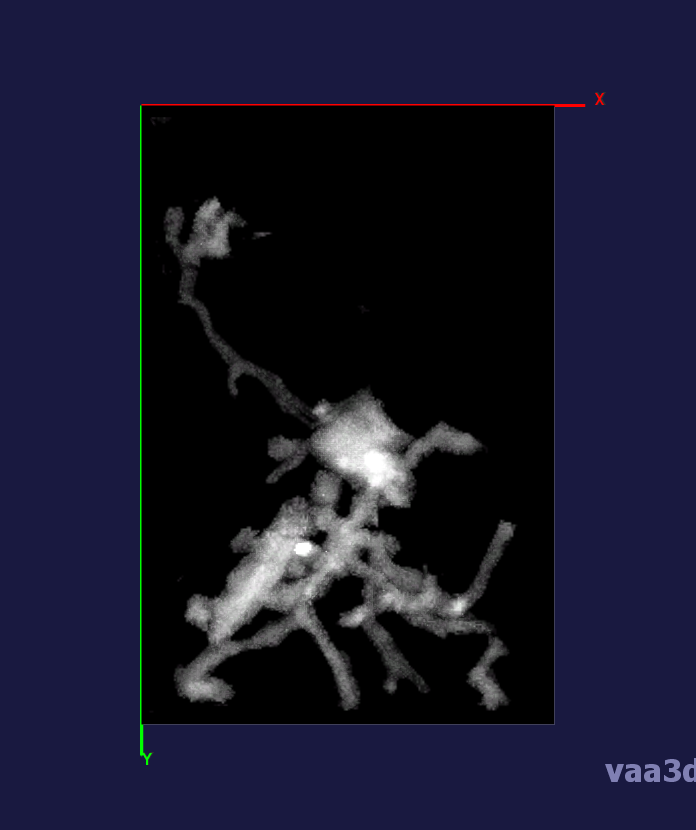

In our experiments, we compare the coupled TuFF-BFF microglia segmentation results with those given by L2S [21] and the Chan-Vese segmentation method [22]. The groundtruth in 3D was attained by manually tracing the object slice by slice from the z-stack. It must be noted that this was done by eye and could have some error. Figure 2 shows the visual comparison of the segmentation results for our dataset. Our result shown on the third column captures both the soma and processes. Figure 3 shows the Dice coefficient comparison of each segmentation method to the ground truth. Since the soma is much larger than the fine processes in the microglia, the processes have less volumetric impact on the similarity score. As explained in Section 1, segmenting the processes is important for quantifying the extension from the soma and its volume of surveillance. We use the Dice coefficient to quantitatively compare the ramification by taking the convex hull of the resulting segmentation. The Dice coefficient is a similarity measure that is computed using with where is the ground truth and is the compared image.

From Figure 4, the average Dice score for coupled TuFF-BFF was 0.77, compared to 0.53 for L2S [21] and .58 for Chan-Vese [22]. It must be noted that L2S required manual user initialization for each 2D image in the stack. While the Chan-Vese method has automatic seed selection, our coupled TuFF/BFF method was the only method that was a true 3D segmentation algorithm. L2S could not consistently capture the entire processes due to the intensity inhomogeneity throughout the object and background noise. The Chan-Vese segmentation could capture the extensions of the processes but did not work well with noise and attained false positives in the reconstruction. Since our method uses the tubular and blob information of the object to separate foreground and background, the segmentation only evolved within the object boundaries.